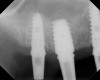

The implant is then delivered and should be well stabilized in the bone. If there is any mobility of the implant, it can either be placed a little deeper (if there is enough native bone) or the implant can be removed and the procedure aborted, in which case it would be a two-stage procedure. This should rarely occur with the tapered designed implant, even with only 2 mm of native bone. Using a bone-level platform-shifting implant (or a tissue-level designed implant) is critical, as the hard and soft tissue will establish a biologic width. If an external hex type of implant is used and the shoulder is placed at the bone level, an expected bone loss of 1.5 mm to 2 mm will occur.24 Figure 10 shows proper bone-level implant depth placement with a platform-shifting design. In this case, a 3-mm healing abutment was placed at the time of surgery to avoid a secondary uncovering surgery, but an implant-level healing abutment could have been placed instead. As can be seen, there was only about 2 mm to 3 mm of native bone height. The membrane was raised about 8 mm to 9 mm. Comparing the radiograph on the day of surgery (Figure 10) to the 6-month postoperative radiograph (Figure 11) shows no loss of native bone, as well as the positive change in appearance of the grafted bone. The 3.5-month CBCT scan (Figure 12) shows good healing of the bone with no coronal bone loss. With minimal native bone present, as in this case, the use of a non-platform-shifting or non-tissue-level implant design could be problematic. After 1.5 mm to 2 mm of crestal bone loss, an external hex designed implant could develop instability with possible implant failure. If a non-tapered implant is used and bone loss occurs during healing, migration of the implant into the sinus could potentially occur. The surgeon can use either a healing abutment or implant-level closure screw over the implant shoulder. With patients who tend to use their tongues to explore or play with the area, or if the area is under a removable partial denture, a closure screw is recommended.

A 74-year-old male patient presented with about 4 mm to 5 mm of native bone in the No. 4 position (Figure 17). A composite graft, as described in Case 1, was used, as was the same implant type, but the implant was 11.5 mm in length with a taper of 5 mm to 4.2 mm. The approximately 16-month post-healed floor of the sinus was raised about 7 mm to 8 mm (Figure 18). The CBCT scan taken at 16 months postoperatively showed no change in appearance from the area of the old floor of the sinus to the new bone formed (Figure 19). Although it was endodontically involved, tooth No. 15 was not extracted, against professional advice. As can be seen in Figure 18, the No. 14 implant is acting as a bridge abutment.

This patient was a 73-year-old man with only about 3.5 mm of native bone in the No. 3 site (Figure 20). The composite graft used here was a 50:50 mixture of DFDBA and deproteinized bovine bone mineral (Osteohealth, www.osteohealth.com) with approximately 40% calcium sulfate added. The implant was the same type and length as in Case 1 above. Figure 21 shows the area on the day of placement. In the CBCT scan on the day of placement (Figure 22), the native bone and bone graft were clearly discernable. However, the postoperative radiograph taken at 6.5 months (Figure 23) showed no marginal bone loss and a significantly denser appearance than when the graft was place. The membrane was raised about 7 mm to 8 mm. The final radiograph was taken after extraction of tooth No. 2 and after extraction of tooth No. 4 and immediate implant placement.